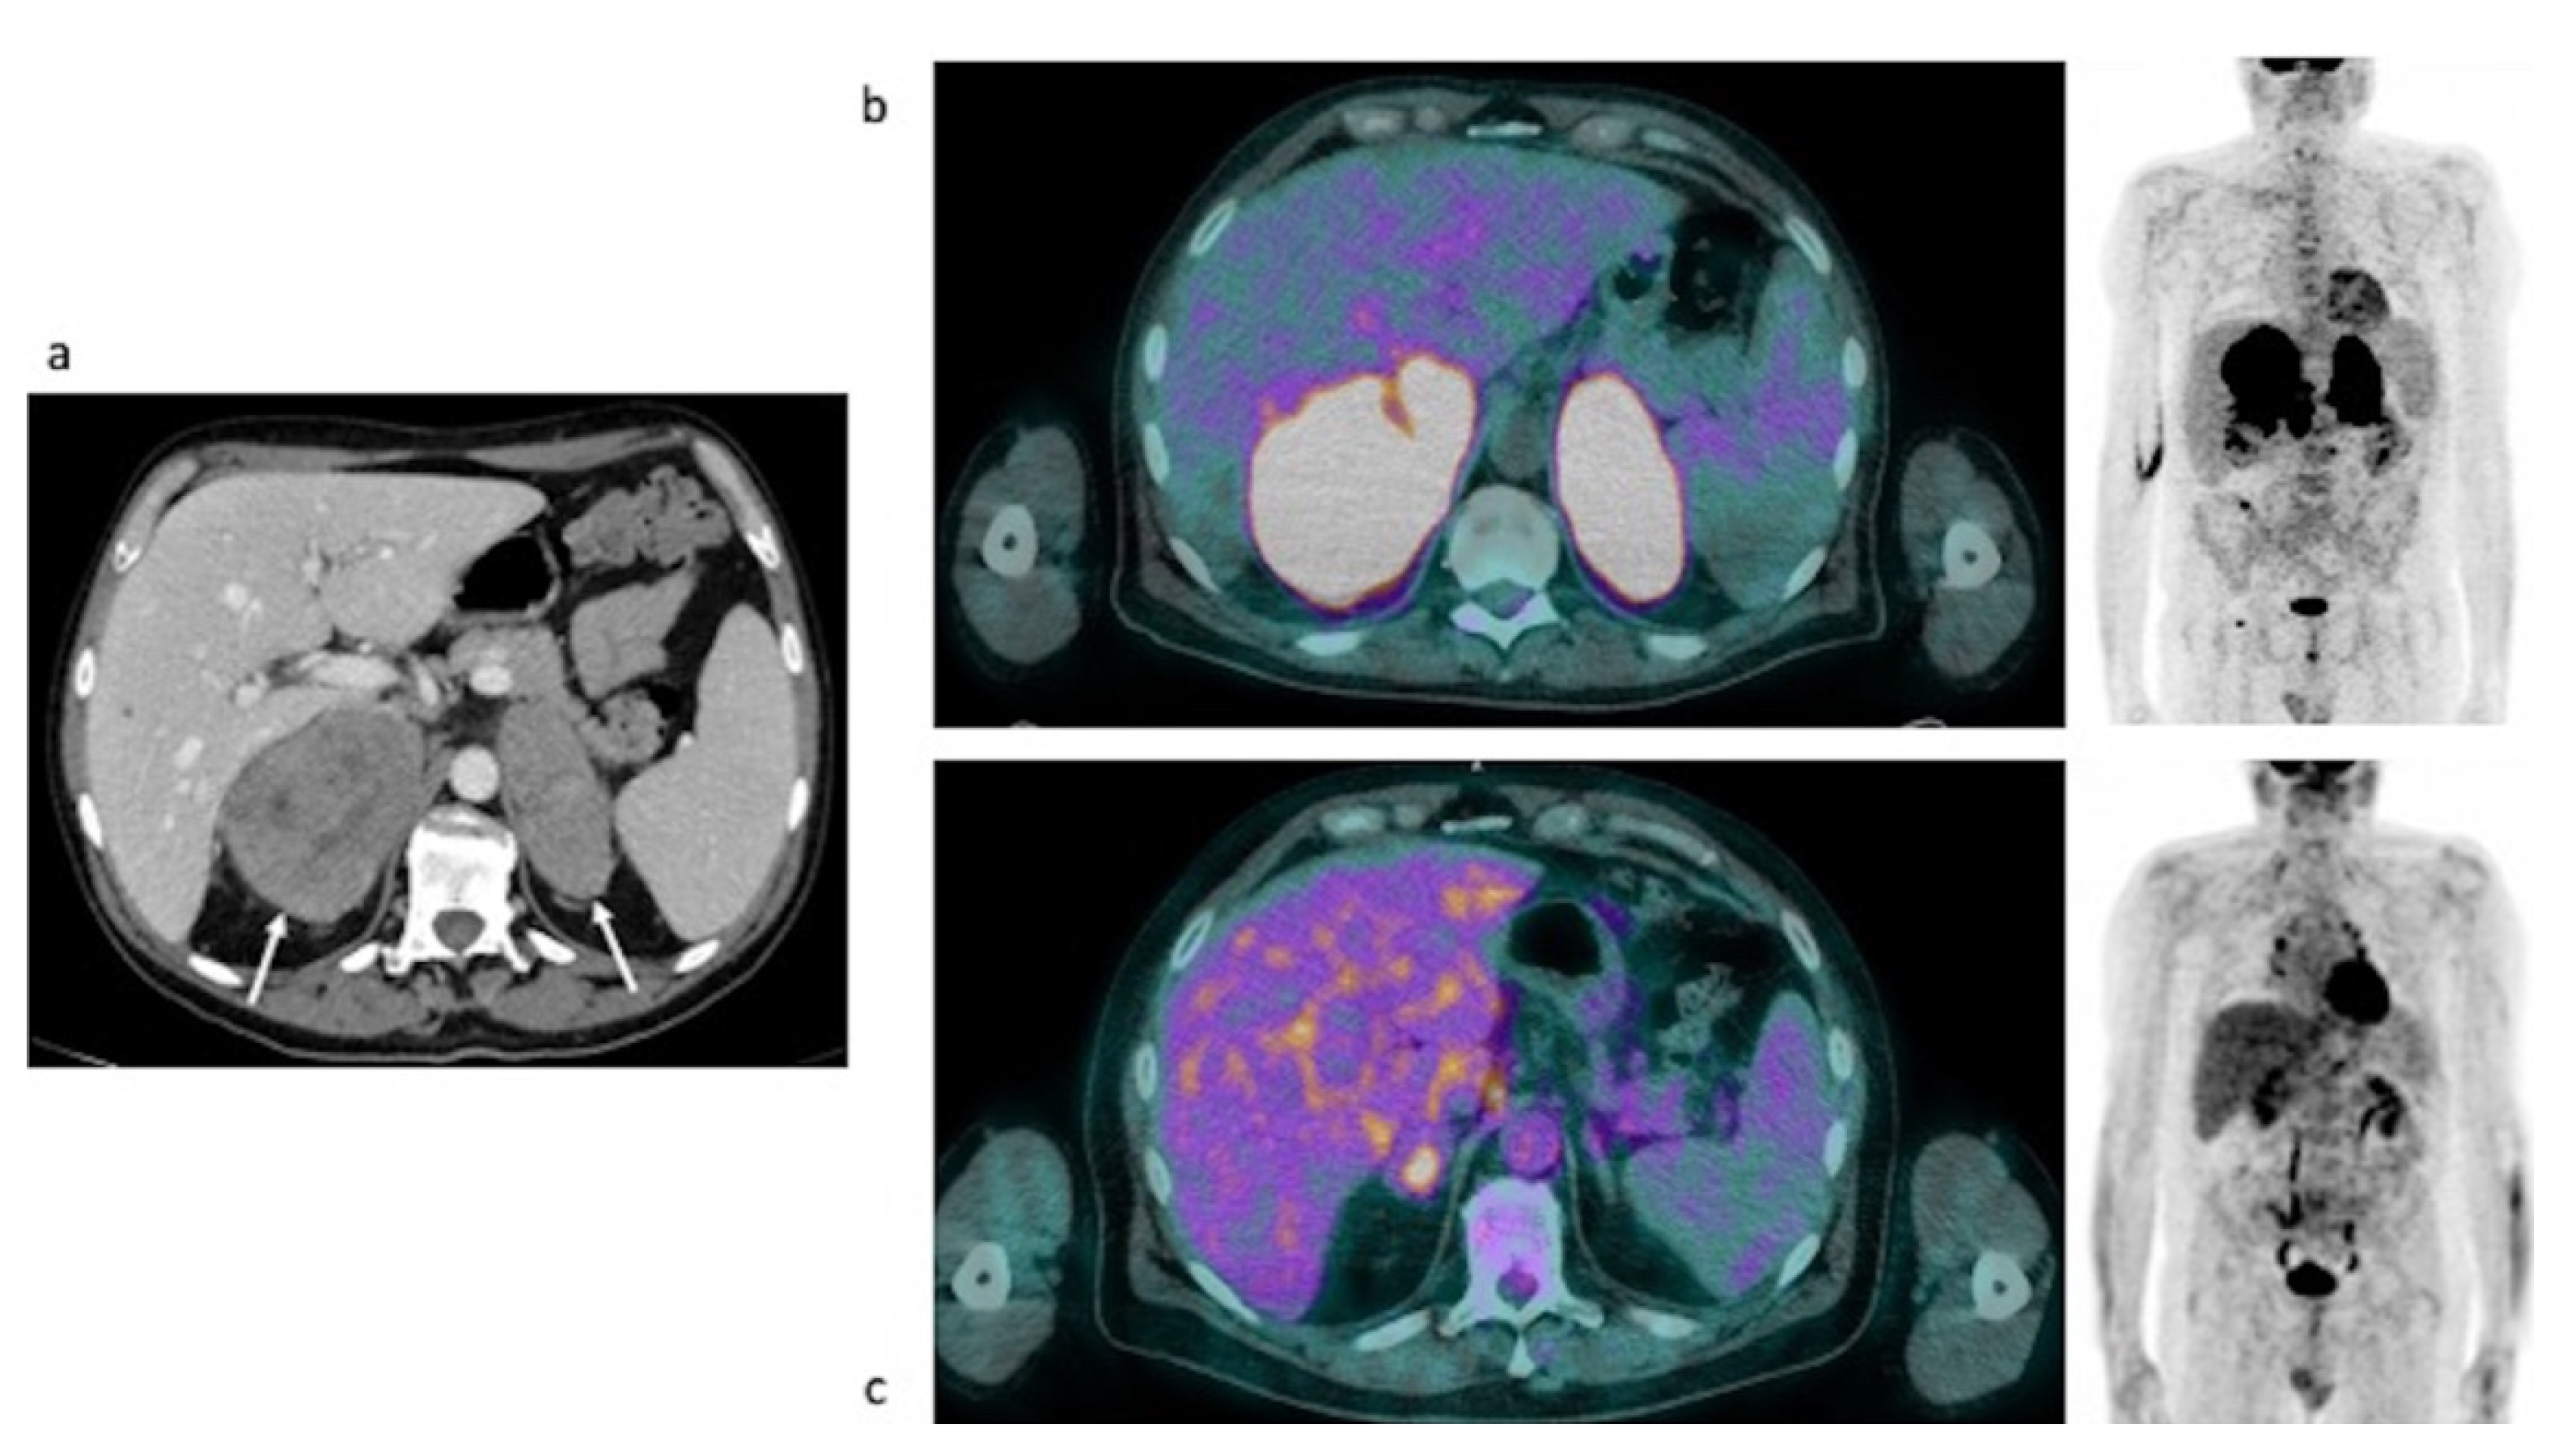

Case #3